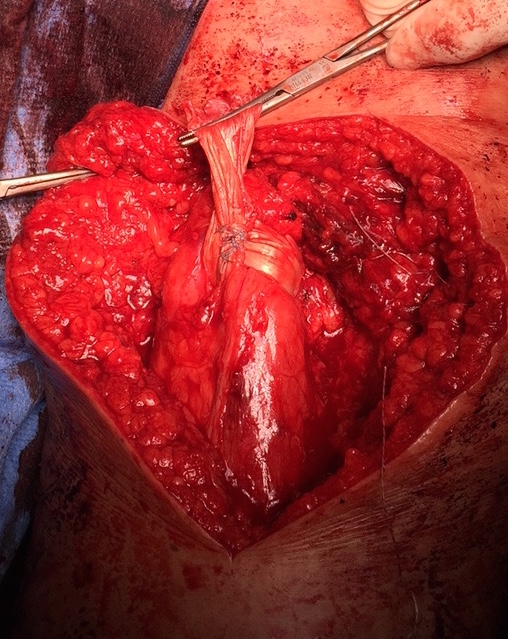

Hamstring (*) with sciatic nerve lateral to hamstring (blue vessiloop)

Identify and release proximal hamstring tendon

Stump of the conjoint tendon (*)